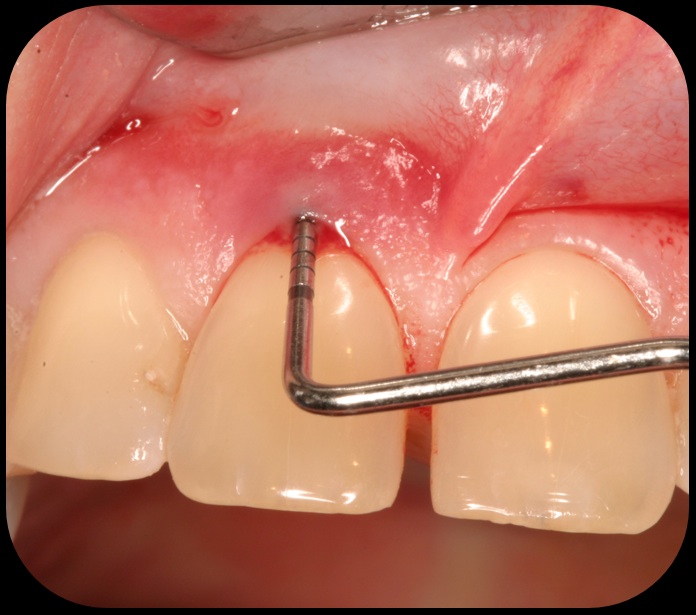

Evidence of clinical attachment gain.

Fig. 6

Then, too, are opportunities to prepare the site for regeneration by coupling therapies, applying an enamel matrix derivative, along with traditional bone grafts of demineralized freeze-dried bone allograft; potentially, gains in attachment with minimal probing depth and retained papilla may avoid the need for an implant (Figure 2 through Figure 7).